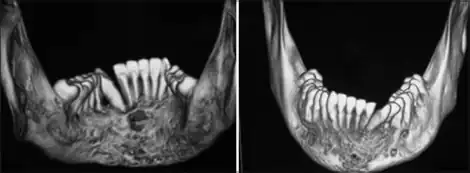

CT scan image showing severe mandibular radiolucency and alveolar bone resorption

The serum concentration of calcifediol, also called 25-hydroxyvitamin D (abbreviated 25(OH)D), is typically used to determine vitamin D status. Most vitamin D is converted to 25(OH)D in the serum, giving an accurate picture of vitamin D status.[55] The level of serum 1,25(OH)D is not usually used to determine vitamin D status because it often is regulated by other hormones in the body such as parathyroid hormone.[55] The levels of 1,25(OH)D can remain normal even when a person may be vitamin D deficient.[55] Serum level of 25(OH)D is the laboratory test ordered to indicate whether or not a person has vitamin D deficiency or insufficiency.[55] It is also considered reasonable to treat at-risk persons with vitamin D supplementation without checking the level of 25(OH)D in the serum, as vitamin D toxicity has only been rarely reported to occur.[55]